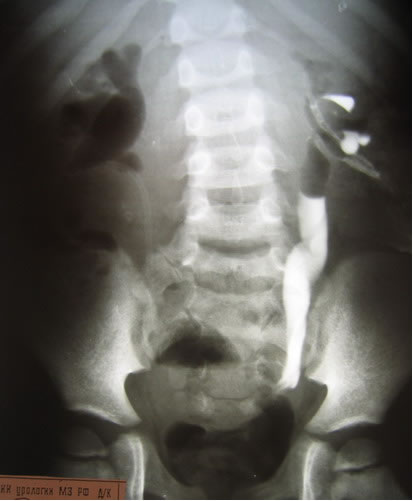

Антеградная уретерография справа